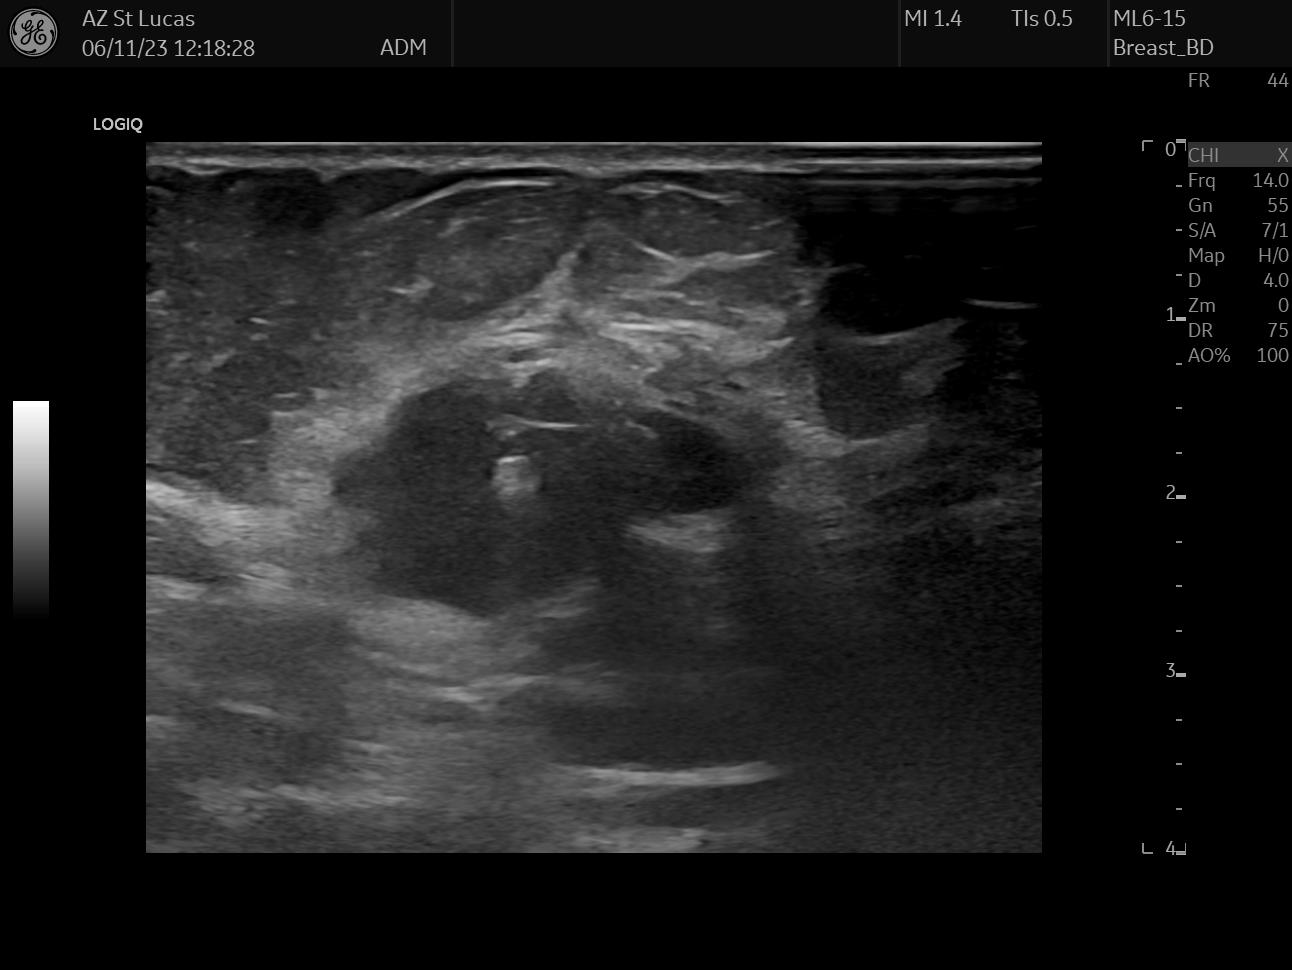

On October 17th 2023 I went to the hospital for an echography; the radiologist asked me almost immediately if they could perform a biopsy. So they stuck a needle in my breast and took out a few tissue samples. It was painful as hell and I ended up crying, confused, and trembling on the bed. The doctor asked me why I went alone for a check of this entity. Well, I didn’t know better, but there was my first lesson:

The data I chose for this day are two scans from the echography, they both clearly show the lesion; the second picture also shows the measurements the radiologist took.